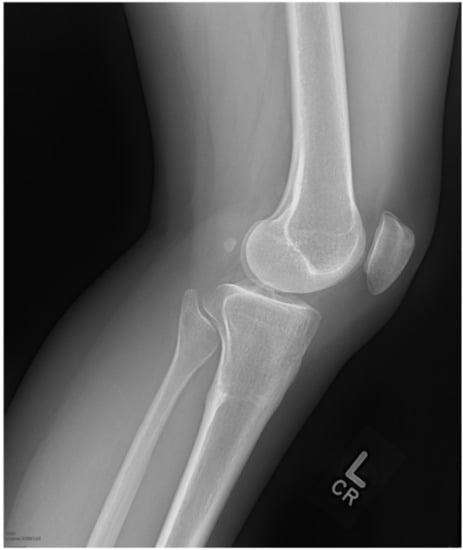

2. Case 1

3. Case 2